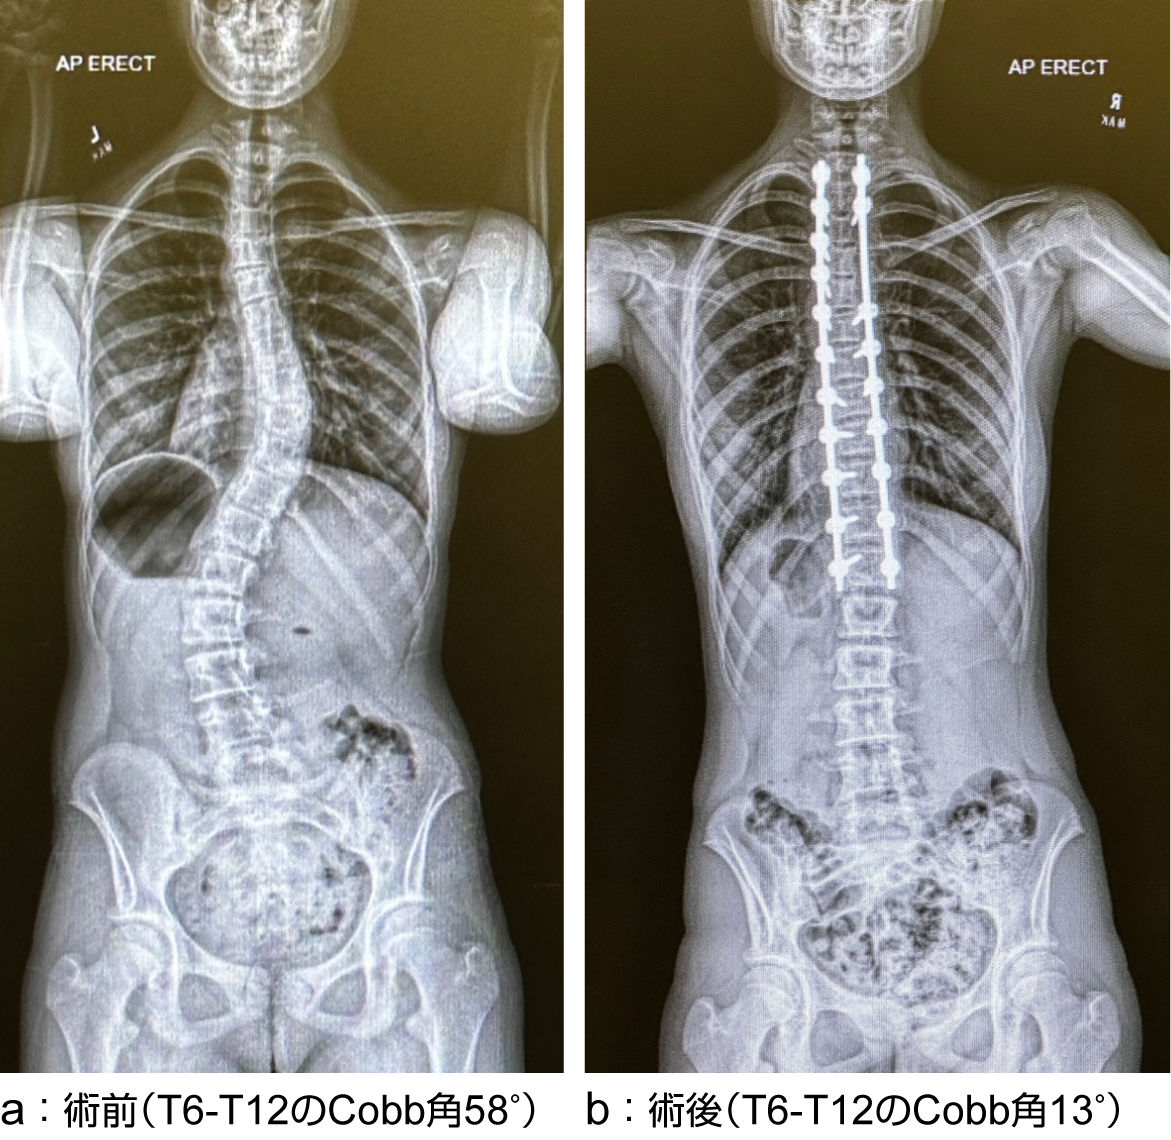

特発性側弯症(胸椎カーブ)の立位全脊柱X線正面像

胸椎にカーブを認めT6- T12のcobb角は58°であったが(a)、後方矯正固定術により、T6- T12のcobb角は13°に改善した(b)。